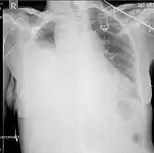

Computed tomography (CT or CAT) scans may be useful for diagnosing retained hemothorax as this form of imaging can detect much smaller amounts of fluid than a plain chest X-ray. However, CT is less used as a primary means of diagnosis within the trauma setting, as these scans require a critically ill person to be transported to a scanner, are slower, and require the subject to remain supine.[23][26]

CT scan of the chest showing a hemothorax caused by warfarin use